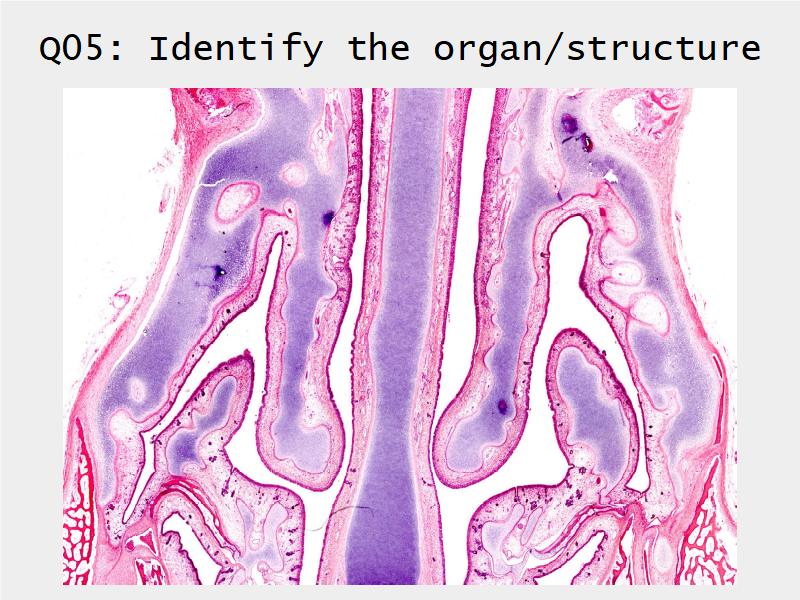

- Slide 73: Trachea

Respiratory epithelium

- Pseudostratified

- Ciliated

- Columnar

- Epithelium with

- 4 Cells

- Ciliated columnar cells

- Non-ciliated columnar cells

- Goblet cells

- Basal cells